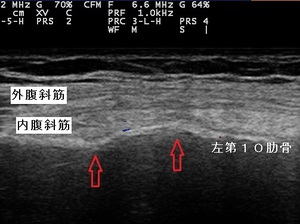

左第10肋骨 超音波長軸像 左同部 レントゲン画像

川越市60代男性、会社員。 肋骨の痛み、肋骨骨折。

当接骨院にて超音波観察を行ったところ、左第10肋骨体部で2か所に骨折が認められました。(左上画像矢印。)

精査依頼先クリニックのレントゲン撮影においても骨折が認められました。(右上画像矢印。) この患者さんは、

転倒したり硬い物が患部にあたった訳でもなかったので、骨折だったことに驚いておられました。

肋骨骨折を起こす原因は、大きく分けて4つあります。

1. 硬いものなどが直接患部にぶつかる場合。

2. 胸郭が前後、左右から圧迫され、肋骨の弾力性により湾曲したところが骨折する場合。

3. 激しい咳やくしゃみ、ゴルフスイングなどの運動による急激な筋収縮により骨折する場合。

4. 上記の原因が複合的に起こる交通事故やスポーツなどのプレー中に起こる場合。

患部の安静を保ち、急な咳やくしゃみなどの負担を軽減、再受傷や悪化を防止するためにバストバンドで

4週前後固定いたします。

また、施術では患部の痛みの緩和、骨癒合促進、骨折周囲の内、外腹斜筋損傷の修復を促す理学療法を

実施いたします。